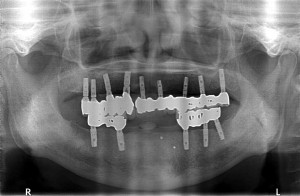

十分に骨は再生しているようでしたが、

上顎洞底骨の厚みは4mmほどしかなかった為、

ソケットリフトを併用してオスフェリオンを填入後、

日本製マイティスアローインプラントB4008sfを埋入させて頂きました。

5ヵ月、または6ヵ月後に最終補綴物を装着させて頂く予定で終了致しました。